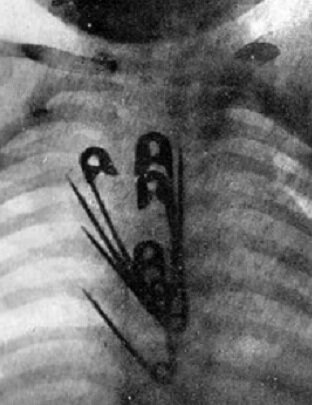

Имеется ввиду информация, что материал, из которого изготовлен оригинальный детский конструктор, содержит сульфат бария. Это вещество притягивает к себе рентгеновские лучи, и делает проглоченные детальки конструктора заметными на рентгеновских снимках. Зная точное местоположение проглоченных пластмассовых деталей в пищеварительном тракте ребёнка, медикам легче и безопаснее извлекать их.